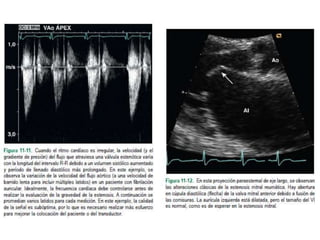

• Si la distensibilidad auricular izquierda o del VI es anormal, el tiempo de hemipresión puede

ser inexacto.